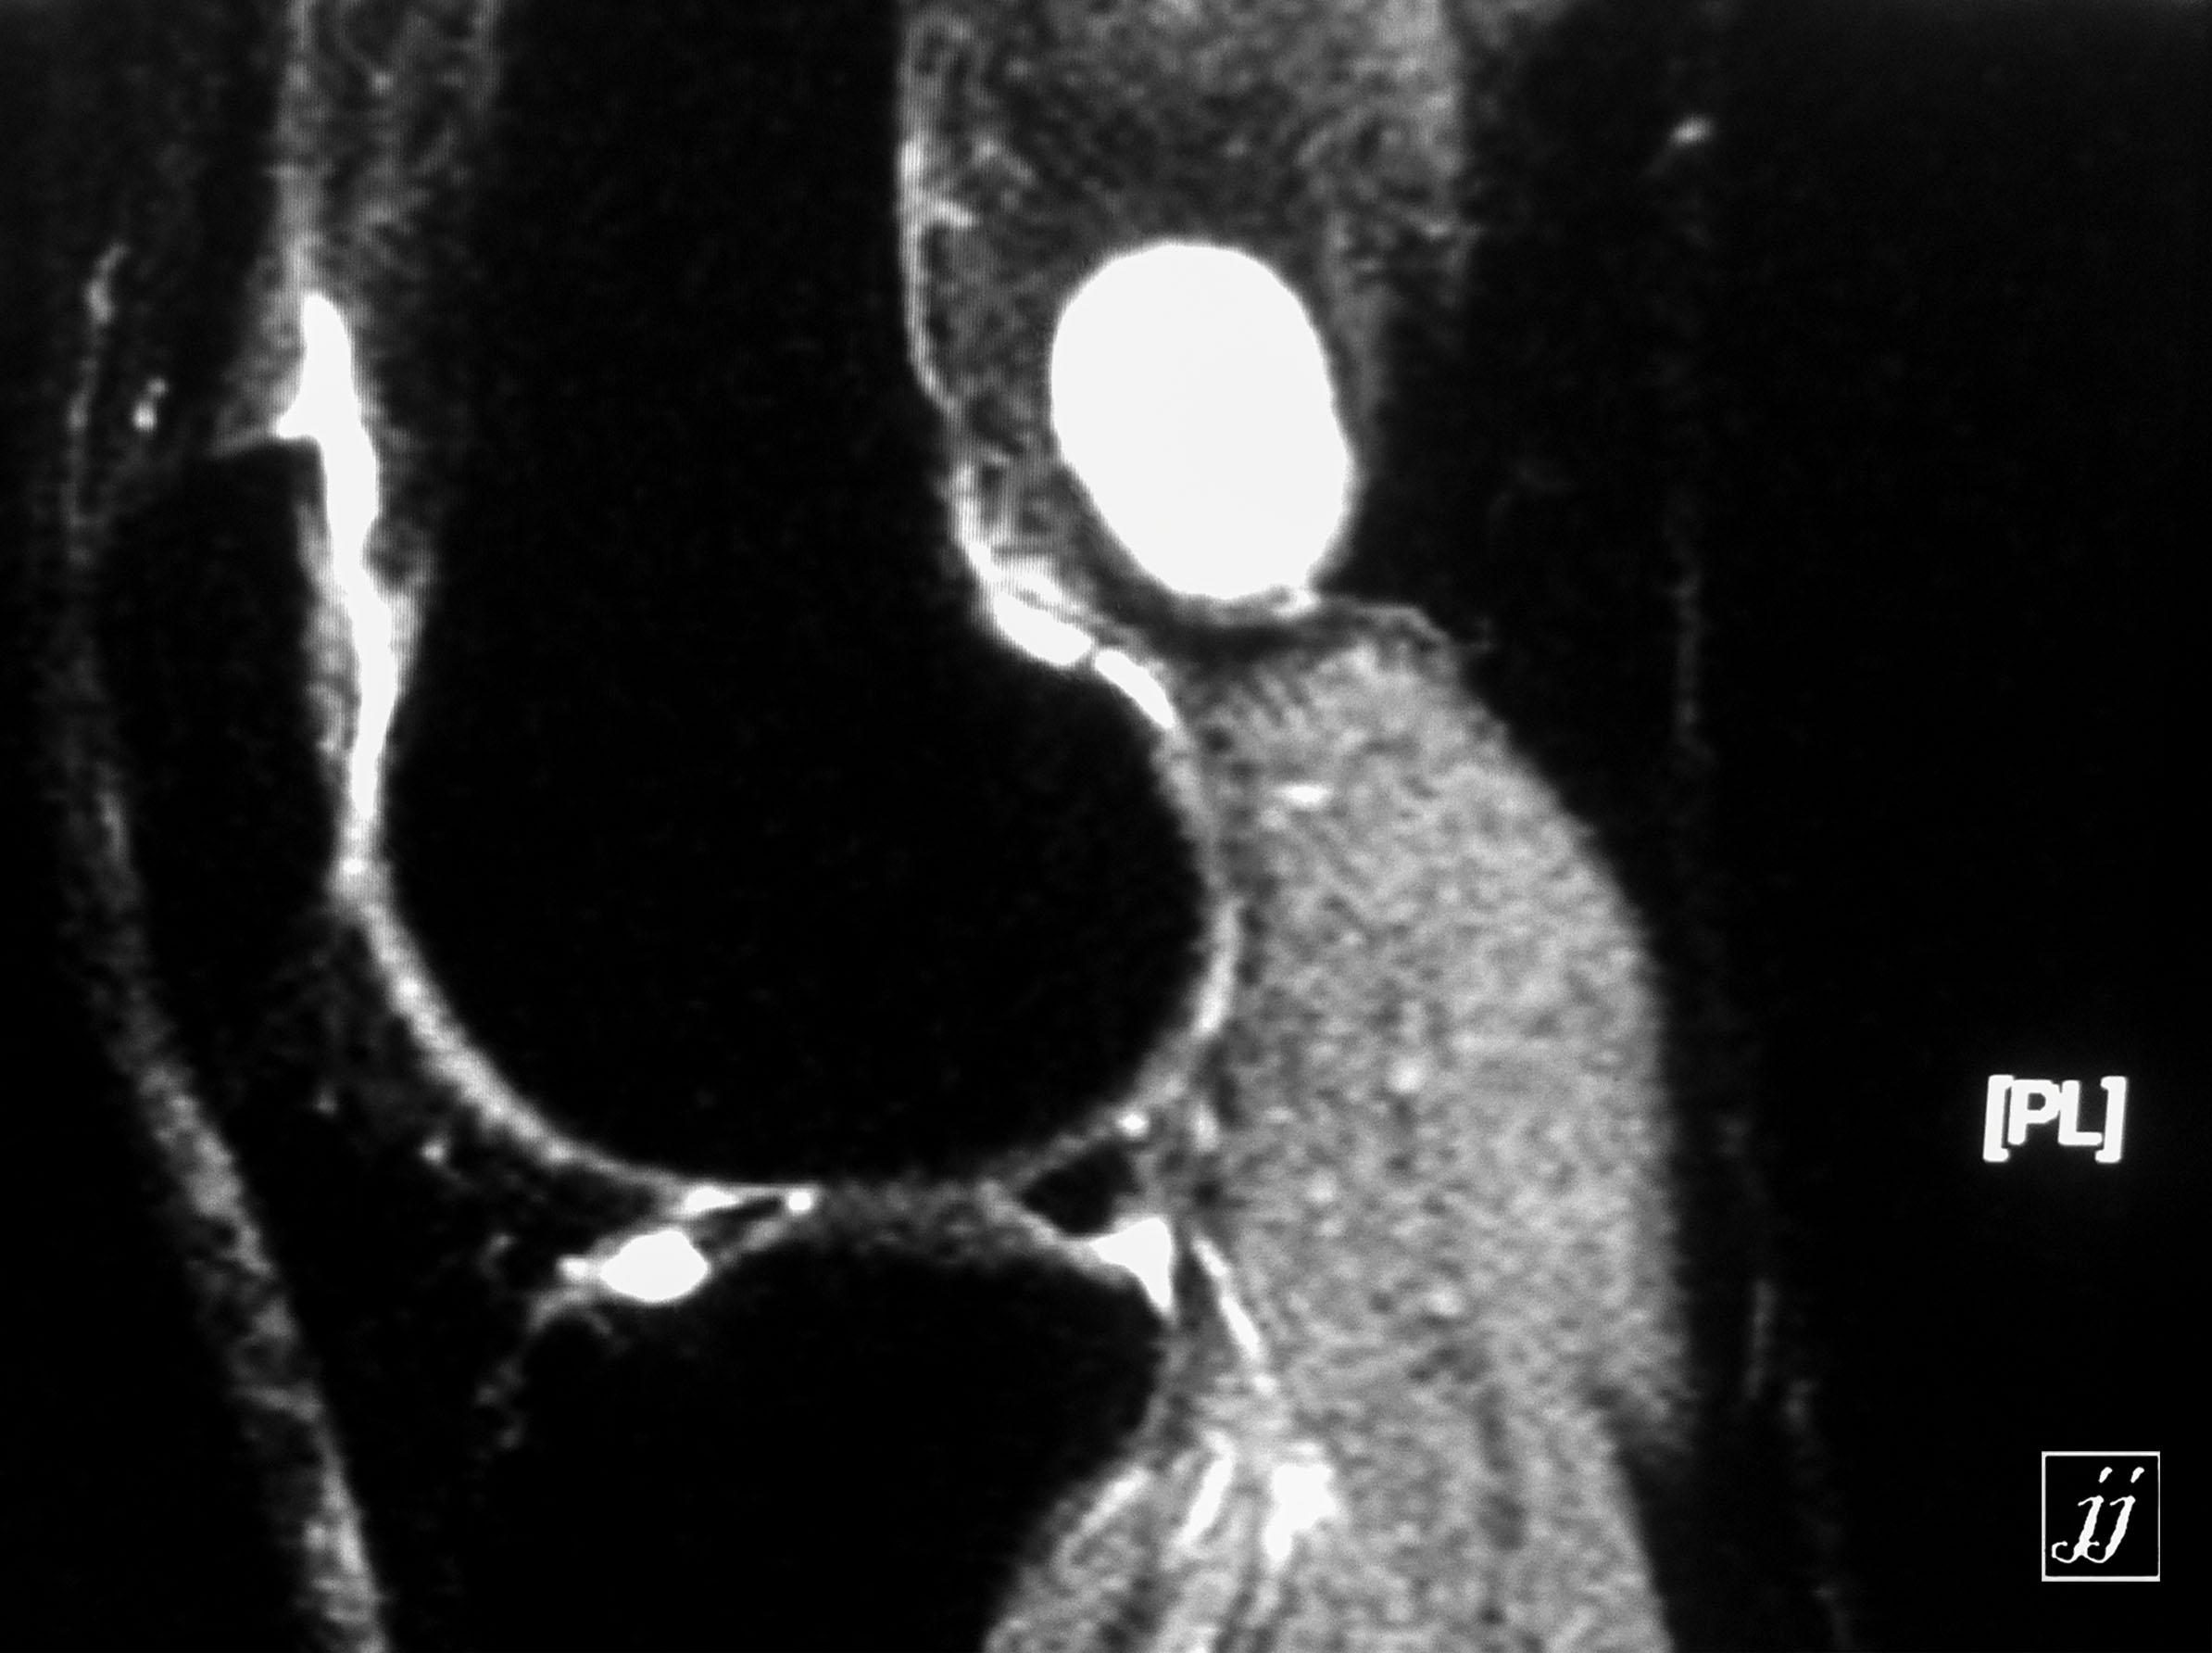

MSK- bi lateral popliteal cyst (3)